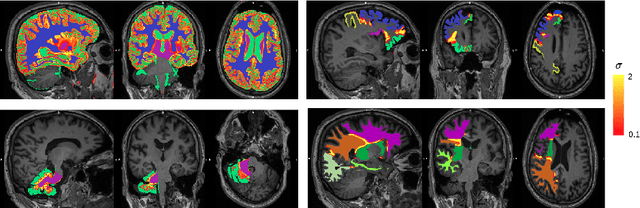

Abstract:Combining multi-site data can strengthen and uncover trends, but is a task that is marred by the influence of site-specific covariates that can bias the data and therefore any downstream analyses. Post-hoc multi-site correction methods exist but have strong assumptions that often do not hold in real-world scenarios. Algorithms should be designed in a way that can account for site-specific effects, such as those that arise from sequence parameter choices, and in instances where generalisation fails, should be able to identify such a failure by means of explicit uncertainty modelling. This body of work showcases such an algorithm, that can become robust to the physics of acquisition in the context of segmentation tasks, while simultaneously modelling uncertainty. We demonstrate that our method not only generalises to complete holdout datasets, preserving segmentation quality, but does so while also accounting for site-specific sequence choices, which also allows it to perform as a harmonisation tool.

Abstract:Being able to adequately process and combine data arising from different sites is crucial in neuroimaging, but is difficult, owing to site, sequence and acquisition-parameter dependent biases. It is important therefore to design algorithms that are not only robust to images of differing contrasts, but also be able to generalise well to unseen ones, with a quantifiable measure of uncertainty. In this paper we demonstrate the efficacy of a physics-informed, uncertainty-aware, segmentation network that employs augmentation-time MR simulations and homogeneous batch feature stratification to achieve acquisition invariance. We show that the proposed approach also accurately extrapolates to out-of-distribution sequence samples, providing well calibrated volumetric bounds on these. We demonstrate a significant improvement in terms of coefficients of variation, backed by uncertainty based volumetric validation.